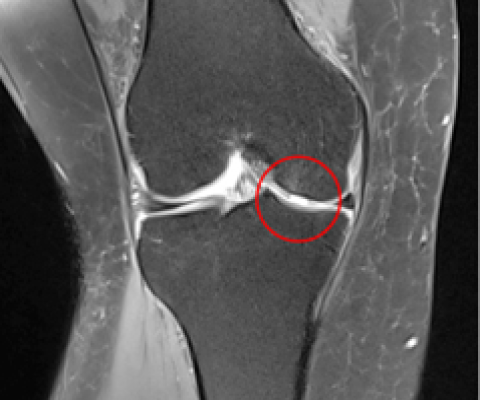

한번 손상된 무릎 연골은 스스로 치유되는 능력이 없어 방치할 경우 지속적으로 연골 결손이 심해지고 통증까지 심해집니다.

새움병원 연골재생술 치료팀에서는 관절내시경을 이용해 손상된 연골을 복구하고 살리는 다양한 치료법을 도입해 퇴행성 관절의 진행을 최대한 늦춰드립니다.

무릎 연골이 손상되면 스스로 재생되지 못하고

나이가 들수록 더욱 연골 결손이 심해집니다.